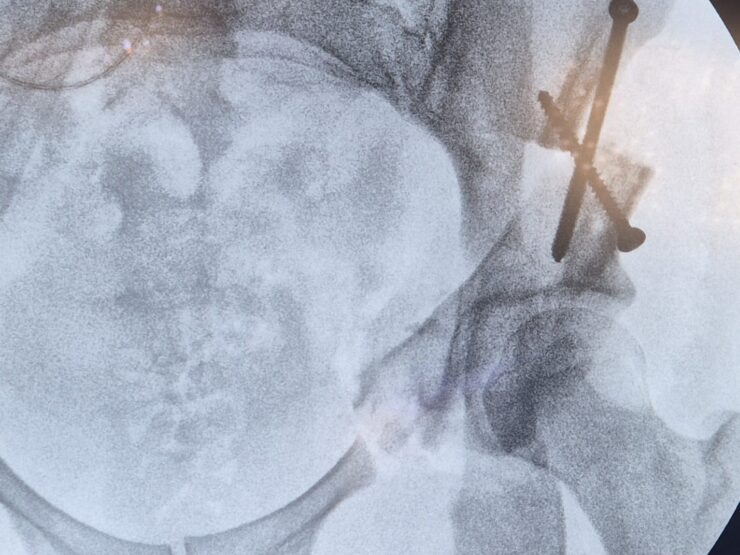

L’articulation est enveloppée d’une membrane malléable mais épaisse et très résistante à la déchirure, appelée capsule articulaire. Celle-ci assure l’étanchéité de l’articulation, empêchant la fuite du liquide synovial. Elle est renforcée par des ligaments puissants reliant l’os du bassin au fémur, de façon circonférentielle.